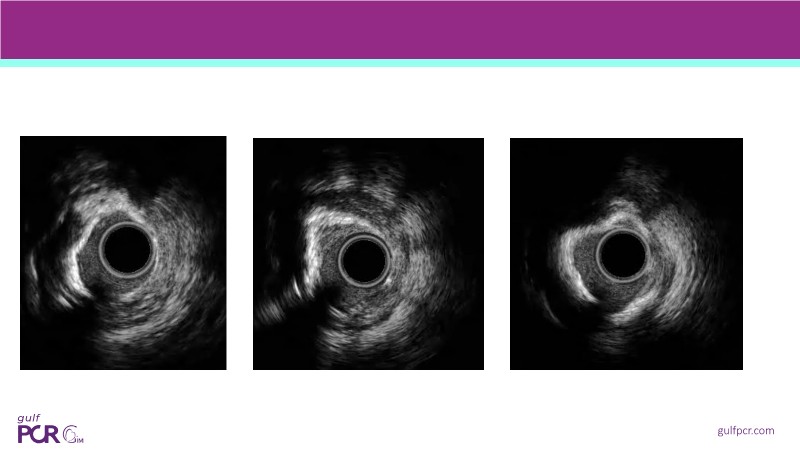

Calcified coronary lesions are a major challenge in PCI. This PCRGulf-GIM 2025 session showcases a complex case with intravascular imaging, highlighting how IVUS 123 guides each step.

From planning the procedure and understanding calcium distribution, to lesion preparation with modern modification tools, and post-PCI assessment to confirm stent expansion and detect complications, this session demonstrates practical, imaging-driven strategies.

Learn how careful preparation and modern techniques improve outcomes in treating severe calcium, calcified nodules, and in-stent restenosis.